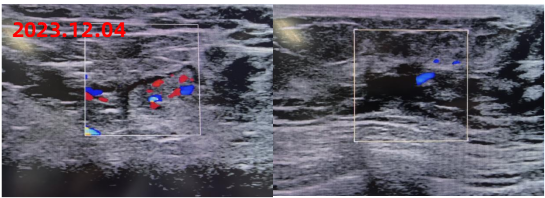

新辅助治疗后影像学复查结果如下:

疗效评价:PR

新辅助治疗反应的评估: 残留癌负荷系统(RCB):RCB分值1.2333,RCB-I级。 Miller-Payne评分系统分级:4级